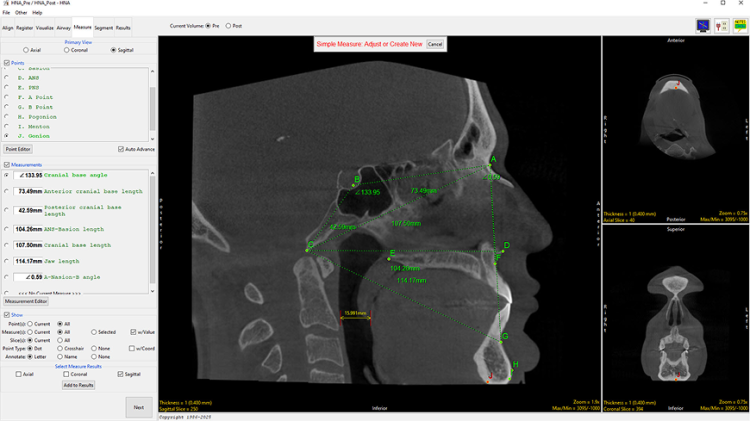

Measure

The Measure tab in the HNA app is designed to perform quantitative analysis of the head and neck, using standard Cephalometric landmarks, which are placed as points on the image.